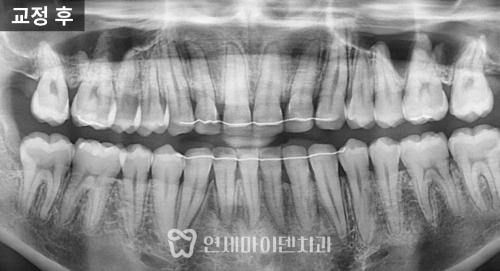

최종 치료 결과

최종적으로 위아래 치아는 가지런하게 배열되었고

왜소치 부위도 라미네이트 보철

심미성과 기능이 보완되었습니다.

치료 기간은 약 2년이 소요되었고,

파노라마 방사선에서도 치근 흡수나 잇몸 손상 없이

안정적으로 마무리되었습니다.